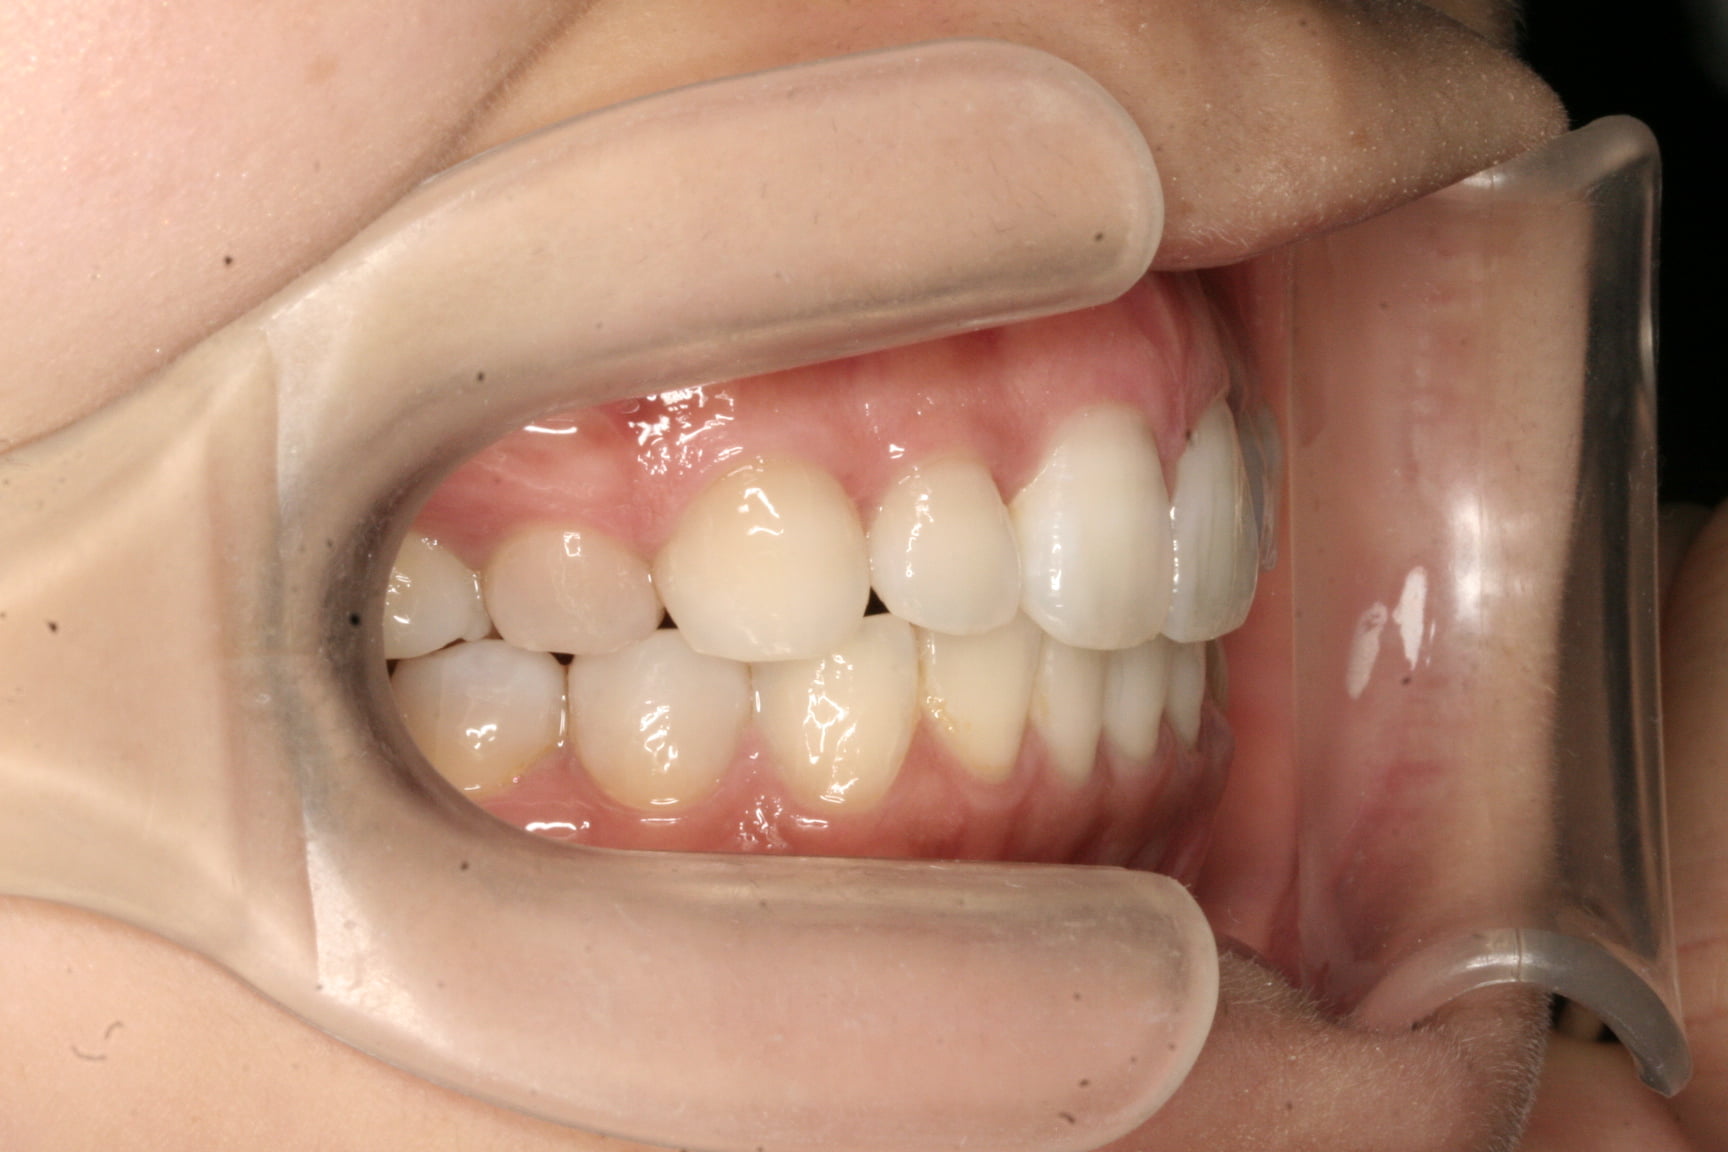

出っ歯を治したい

年齢層 20代

性別 男性

主訴 【主訴】出っ歯を治したい 【診断・症状】上下凸凹、出っ歯(上顎前突)

治療費用 検査・診断:38,500-/裏側矯正治療:1,397,000-(※全て税込)

治療期間 約1年半(20回)

抜歯 有(上4,4のみ)

矯正の装置 裏側矯正(舌側矯正)

副作用、リスク 歯肉退縮,歯根吸収,疼痛,咬合の違和感,装置の違和感,虫歯,歯肉炎

case15_出っ歯_after

After